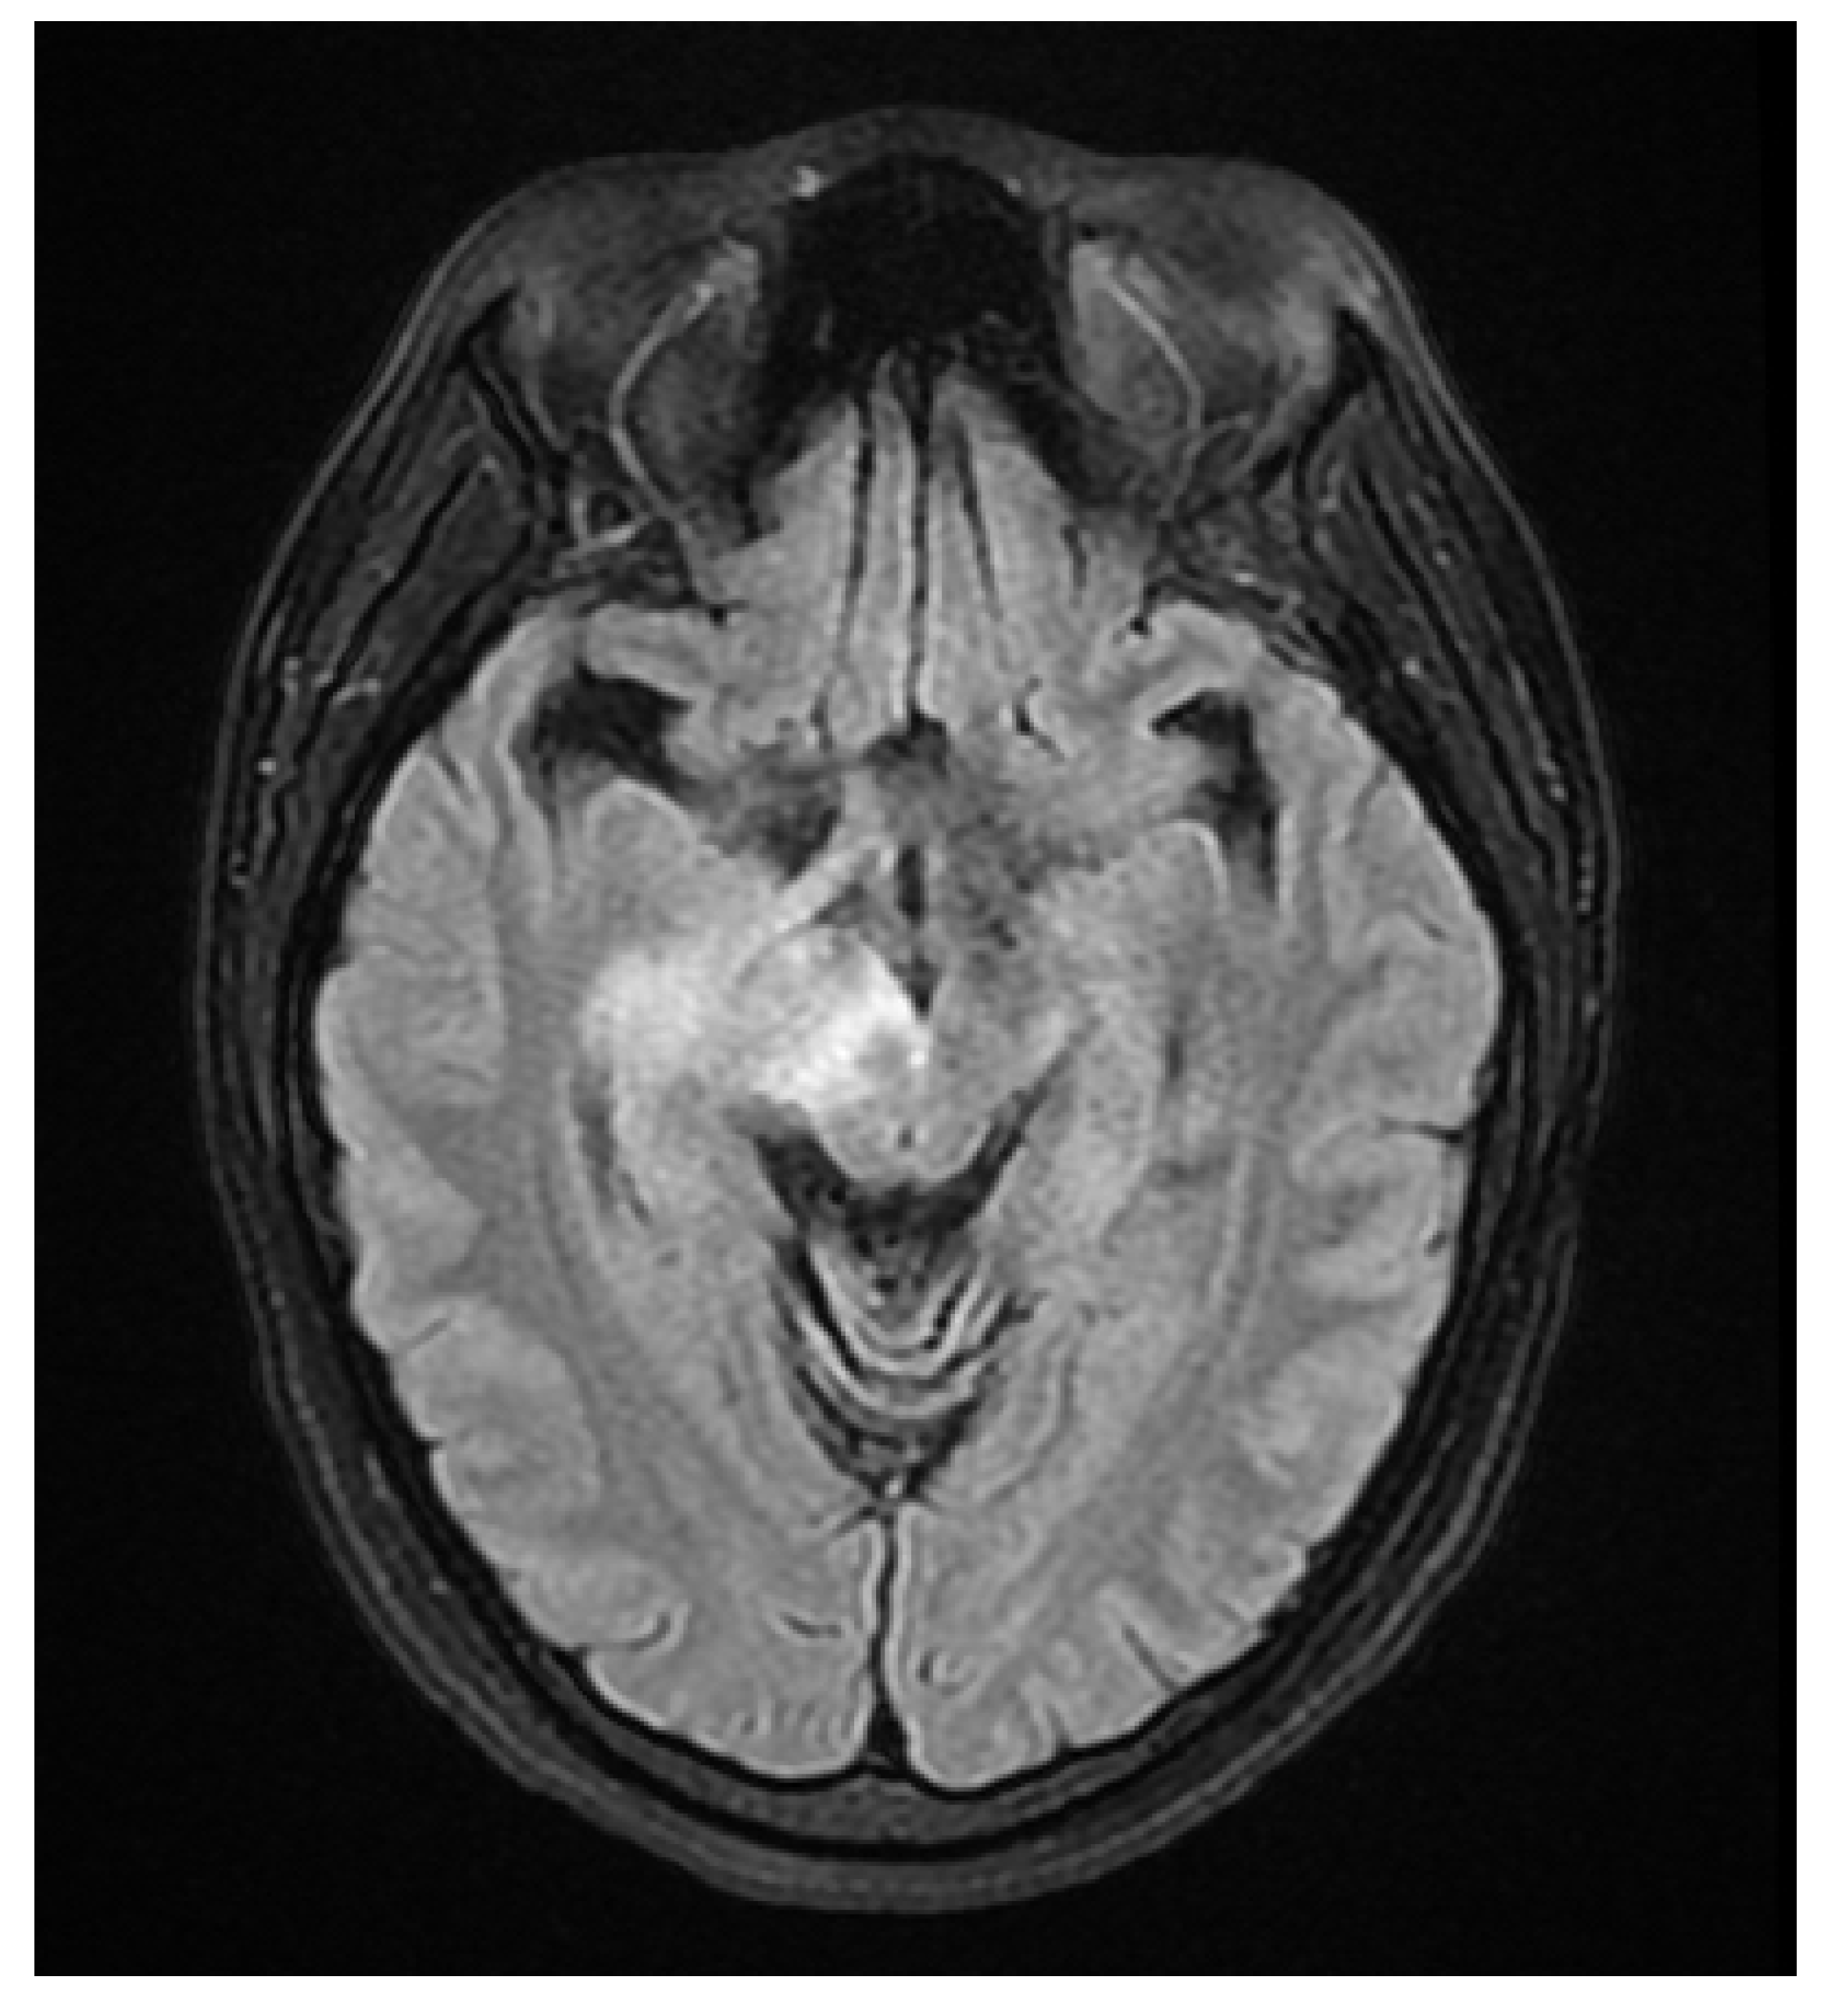

A 37 year old female presented to our hospital due to new onset severe headaches and right sided weakness with facial droop. The patient did not have any significant past medical history before this point. Patient was unable to speak properly and was found to have decreased responsiveness at bedside. Initial CT scan of the head without contrast revealed ill-defined edema involving the left periatrial white matter, involving the central gray matter and external limited internal capsule. MRI head with T2 Flair revealed diffuse edema and inflammation throughout the brainstem, pons, midbrain, and basal ganglia (Figure 1, Figure 2, Figure 3 and Figure 4). EEG showed diffuse slowing suggestive of moderate diffuse cerebral dysfunction without evidence of seizures or epileptiform activity. Lumbar puncture demonstrated a normal opening pressure, with CSF containing 2 red blood cells, 9 white blood cells of which 94% were lymphocytes, glucose of 58, and protein of 42. CSF bacterial cultures were negative, along with no evidence of active HSV or EBV infection. RPR was also negative. Pulse dose steroids were initiated in the ICU. Patient was slow to improve and was transferred to the neurological intensive care unit for further management. After 17 days in the ICU patient was discharged to a rehabilitation facility. Patient slowly improved with physical therapy but did continue to have some refractory lower extremity weakness. At the time of discharge, our patient was discharged on 20mg prednisone daily. Outpatient brain biopsy of the right frontal cortex revealed moderate gliosis but no abnormal lymphocytic infiltration. After thorough review of imaging findings and clinical presentation a diagnosis of acute disseminated encephalomyelitis was made by Neurology.

Figure 4. Flair Axial MRI image reveals white matter lesions in the pons.